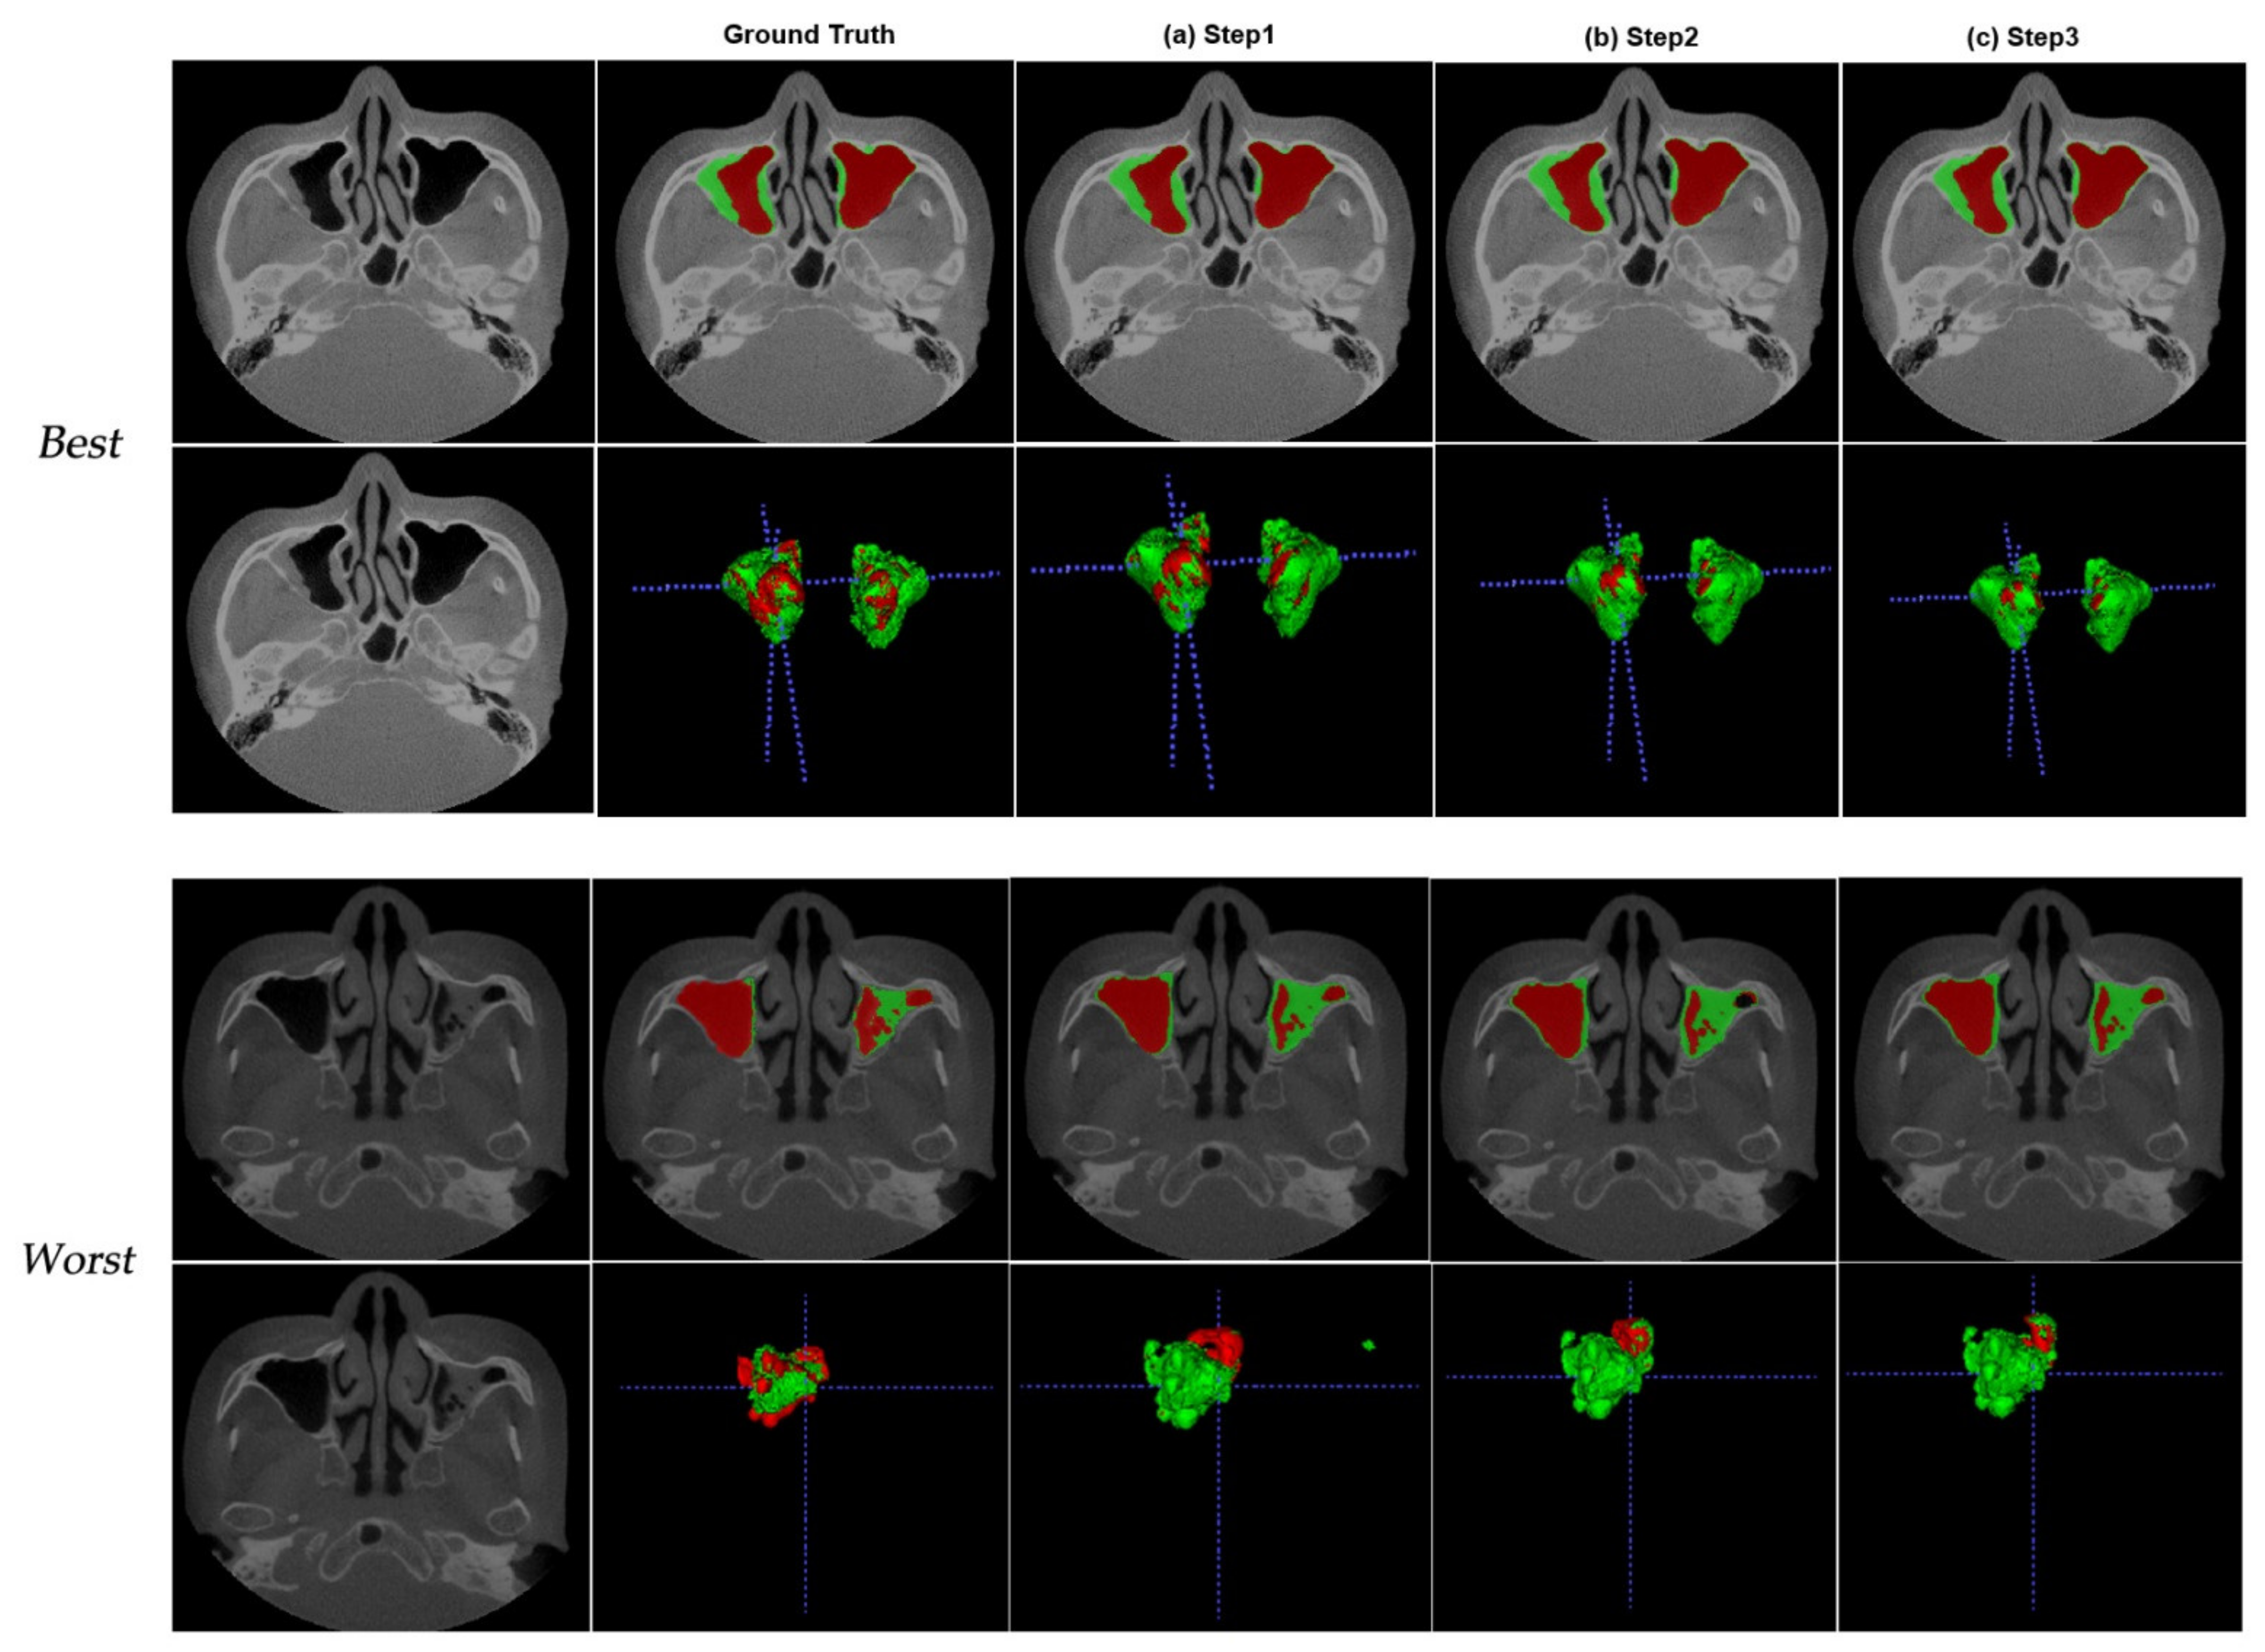

| Mean ± SD (Range) | First Step | Second Step | Last Step |

|---|---|---|---|

| Air | 0.920 ± 0.17 (0.245–0.992) | 0.925 ± 0.16 (0.241–0.991) | 0.930 ± 0.16 (0.243–0.996) |

| Lesion | 0.770 ± 0.18 (0.208–0.912) | 0.750 ± 0.19 (0.205–0.975) | 0.760 ± 0.18 (0.208–0.96) |